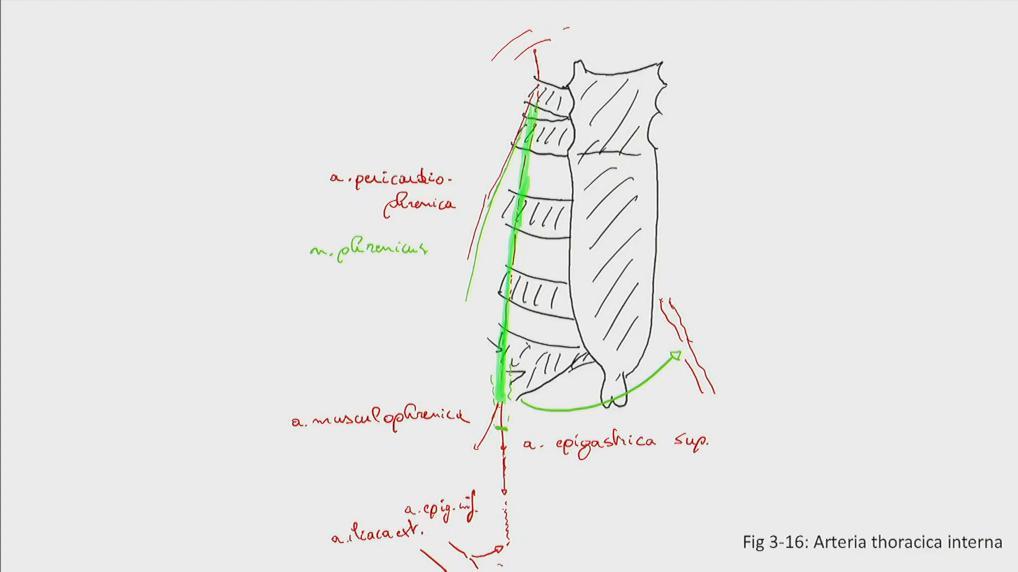

Fig 3.16: a. thoracica interna

|

|